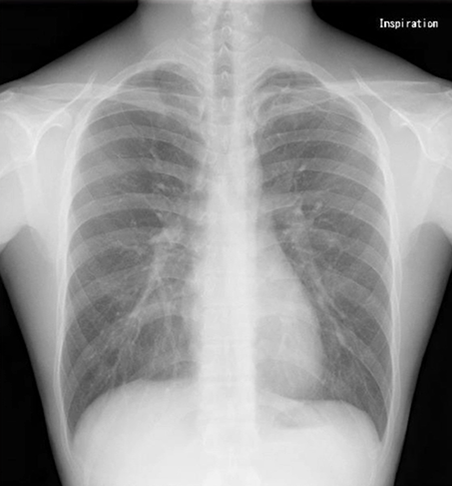

気胸を疑った場合、どのようなレントゲン所見になるのでしょうか。

下記のような特徴があります。

しぼんだ肺(虚脱した肺):

本来肺があるべき範囲に空気しかなく、肺組織自体は「白く」映ります。

胸腔内の空気(黒く見える部分):

肺から漏れ出た空気が肺の外側に溜まり、この空気が「黒く」映ります。

肺紋理(肺の血管走行)の変化:

正常な肺では、血管の走行である肺紋理が肺の隅々まで見えますが、気胸があると肺がしぼんだ部分では肺紋理が見えなくなります。

重症度の判断:

肺のしぼみ具合(虚脱の程度)によって、軽度、中等度、高度気胸と判断されます。肺がさらにしぼんで心臓などを圧迫する重症なケースでは、縦隔という胸の中心が反対側に押し込まれる(縦隔の偏位)所見が見られることもあります。

本症例では左肺尖部の概則に凹凸を認め、気胸を疑います。